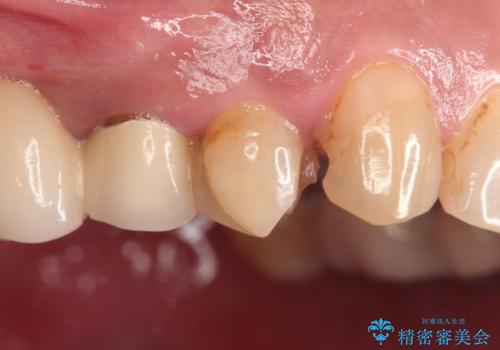

- 以前治療したセラミックインレーが破折したことを主訴に来院されました。

咬合力が強く、残存歯質が少ないためオールセラミッククラウンによる治療を行いました。

咬合力が強くかかる部分には欠けるリスクのほとんどない金属を用いることが最良ですが審美性に劣ります。

今回は白い材料での修復を希望されたため、欠けるリスクが高いセラミックインレーは避け、セラミッククラウンにて治療を行いました。